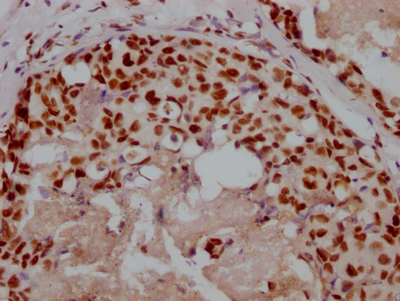

Immunohistochemical analysis of paraffin-embedded Human-testis, antibody was diluted at 1:100

Immunohistochemical analysis of paraffin-embedded Human-testis, antibody was diluted at 1:100